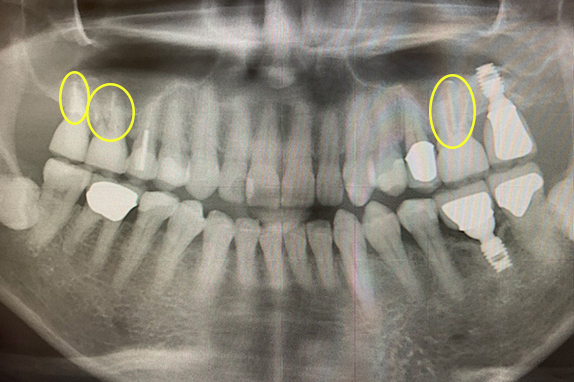

CASE 01 歯周再生治療

-

- 主訴

- 歯がグラグラで噛めない

-

- 回数期間

- 5回 約1年

-

- 治療法

- 歯周再生治療

-

- 治療費用

- 約17万円(税抜)

歯がグラグラで噛めないという主訴の患者様に歯周再生治療を用いて改善したケースです。レントゲン写真をみると術前は歯肉の退縮が見られるが、術後は歯肉の退縮が改善しています。

<リスク・副作用>

手術後は腫れ、痛み、痺れなどの副作用が生じる場合があります。